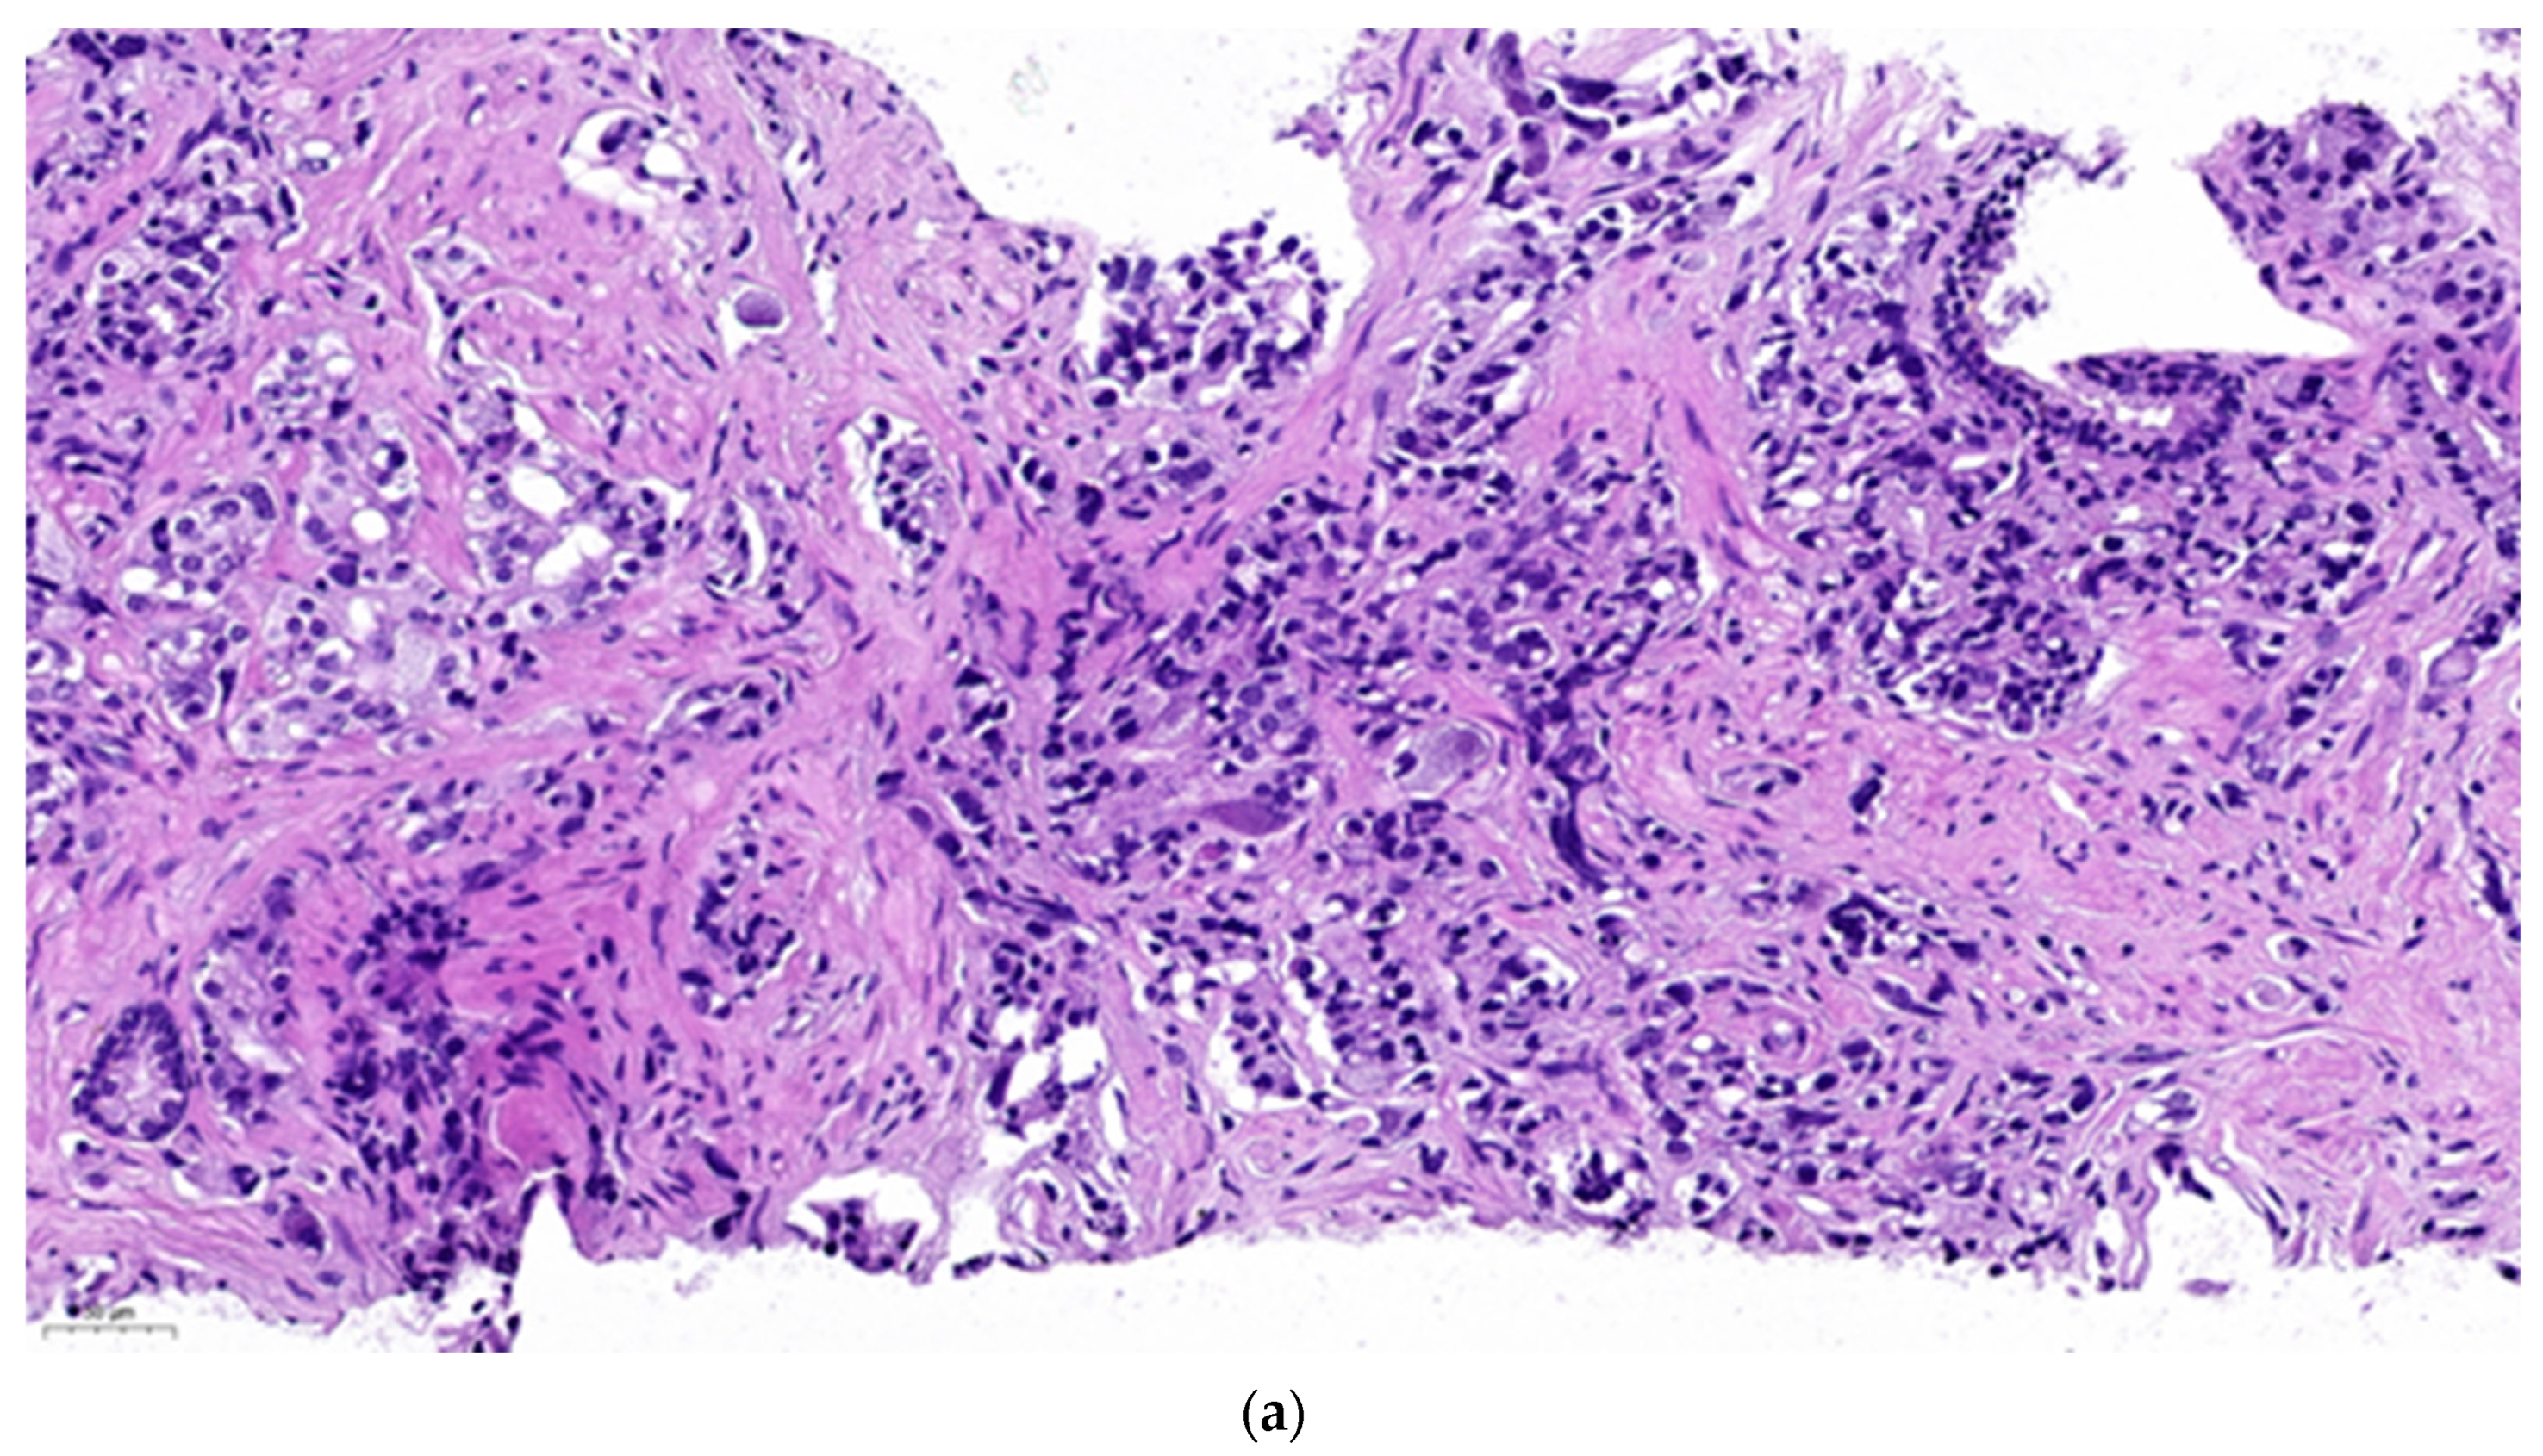

Figure 1 represents isolated neuroendocrine cells within an acinar adenocarcinoma (Gleason grade group 3) in a prostate biopsy specimen. The density of the neuroendocrine cells is not higher in the cancer than in the normal prostatic tissue. However, it can not be excluded that one of them might be the source of a malignant neuroendocrine line. The patient received 74 Gy radiotherapy to the prostate. A year later he was diagnosed in another hospital with intermediate grade neuroendocrine cancer affecting paraaortic lymph nodes and the liver, localisations of predilection for metastatic NECP. Since no primary tumour was found the suspicion that the earlier diagnosed prostate cancer be the origin may be raised.

Figure 1. Biopsy specimen of a prostatic acinar adenocarcinoma. (a). Haematoxylin-eosin staining. (b). Chromogranine A immunohistochemistry showing a positive cell in the malignant zone. (c). Chromogranine A immunohistochemistry showing two positive cells in the normal glandular zone.